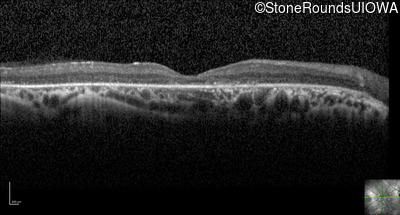

Optical Coherence Tomography - Right - 20/63 +1

Exemplar / OCT Stack